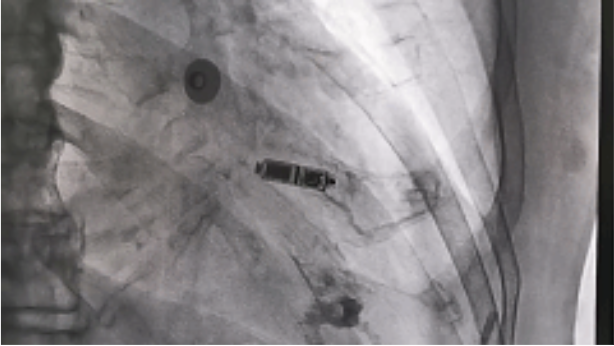

经过充分的术前准备,Micra无导线起搏器植入手术在局部麻醉下进行,通过股静脉穿刺,将起搏器通过导管植入到心腔内部,手术过程仅用半小时,术后体外程控测定各项参数良好。该起搏器无需植入心内膜导线,也无需在胸前皮下制作囊袋,减少了创伤与感染风险。而且Micra无导线起搏器直接植入在心腔内,无伤疤、无切口,患者术后几乎感觉不到起搏器的存在,无需制动,不影响患者日常生活,大大改善了患者的生存质量。

相较于传统起搏器,该无导线起搏器体积减小了93%,仅有胶囊大小,重量仅约2g,且拥有超强的电池续航能力寿命超过12年,同时兼容1.5T(特斯拉)/3.0T核磁共振扫描,可以为心脏提供持续稳定的起搏。